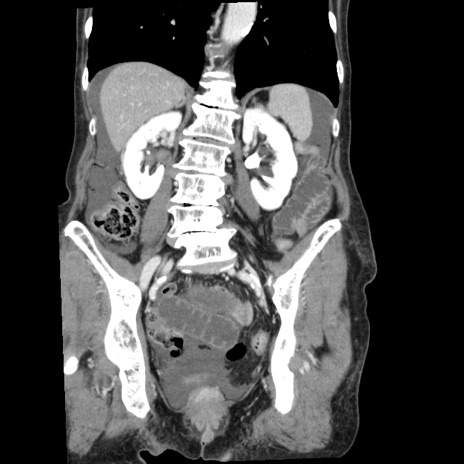

症例1(冠状断像)

【症例】80歳代女性

【主訴】腹痛

【現病歴】8時間前から腹痛あり来院。

【既往歴】糖尿病、脂質異常症、子宮体癌にて子宮全摘術

【身体所見】意識清明・会話良好だが腹痛で苦悶様、全腹部にわたって反跳痛と圧痛あり

【データ】WBC 13600、CRP 0.14、LDH 224、CK 90